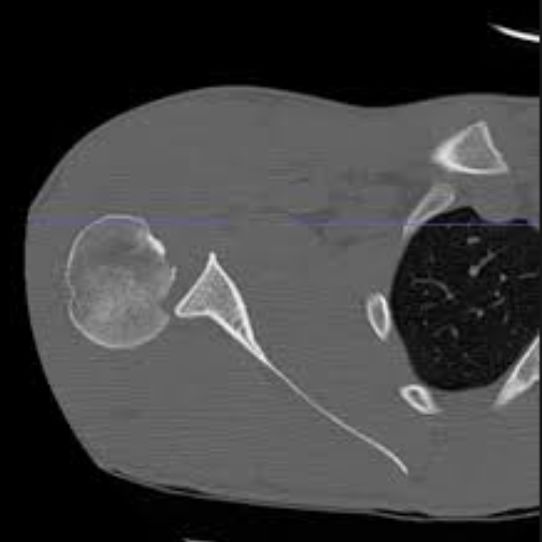

胸锁关节脱位

常规锁骨拍片难以发现胸锁关节脱位,如果是前脱位查体时明显,注意查体以及锁骨 CT 水平位了解胸锁关节脱位及锁骨胸骨端骨折的存在。

胸锁关节后脱位